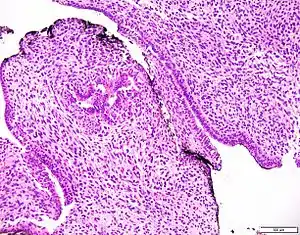

| Prostatic stromal tumour of uncertain malignant potential. H&E stain. | |

Prostatic stromal tumour of uncertain malignant potential (PSTUMP) is a rare tumour of the prostate gland stroma that may behave benign or like cancer.